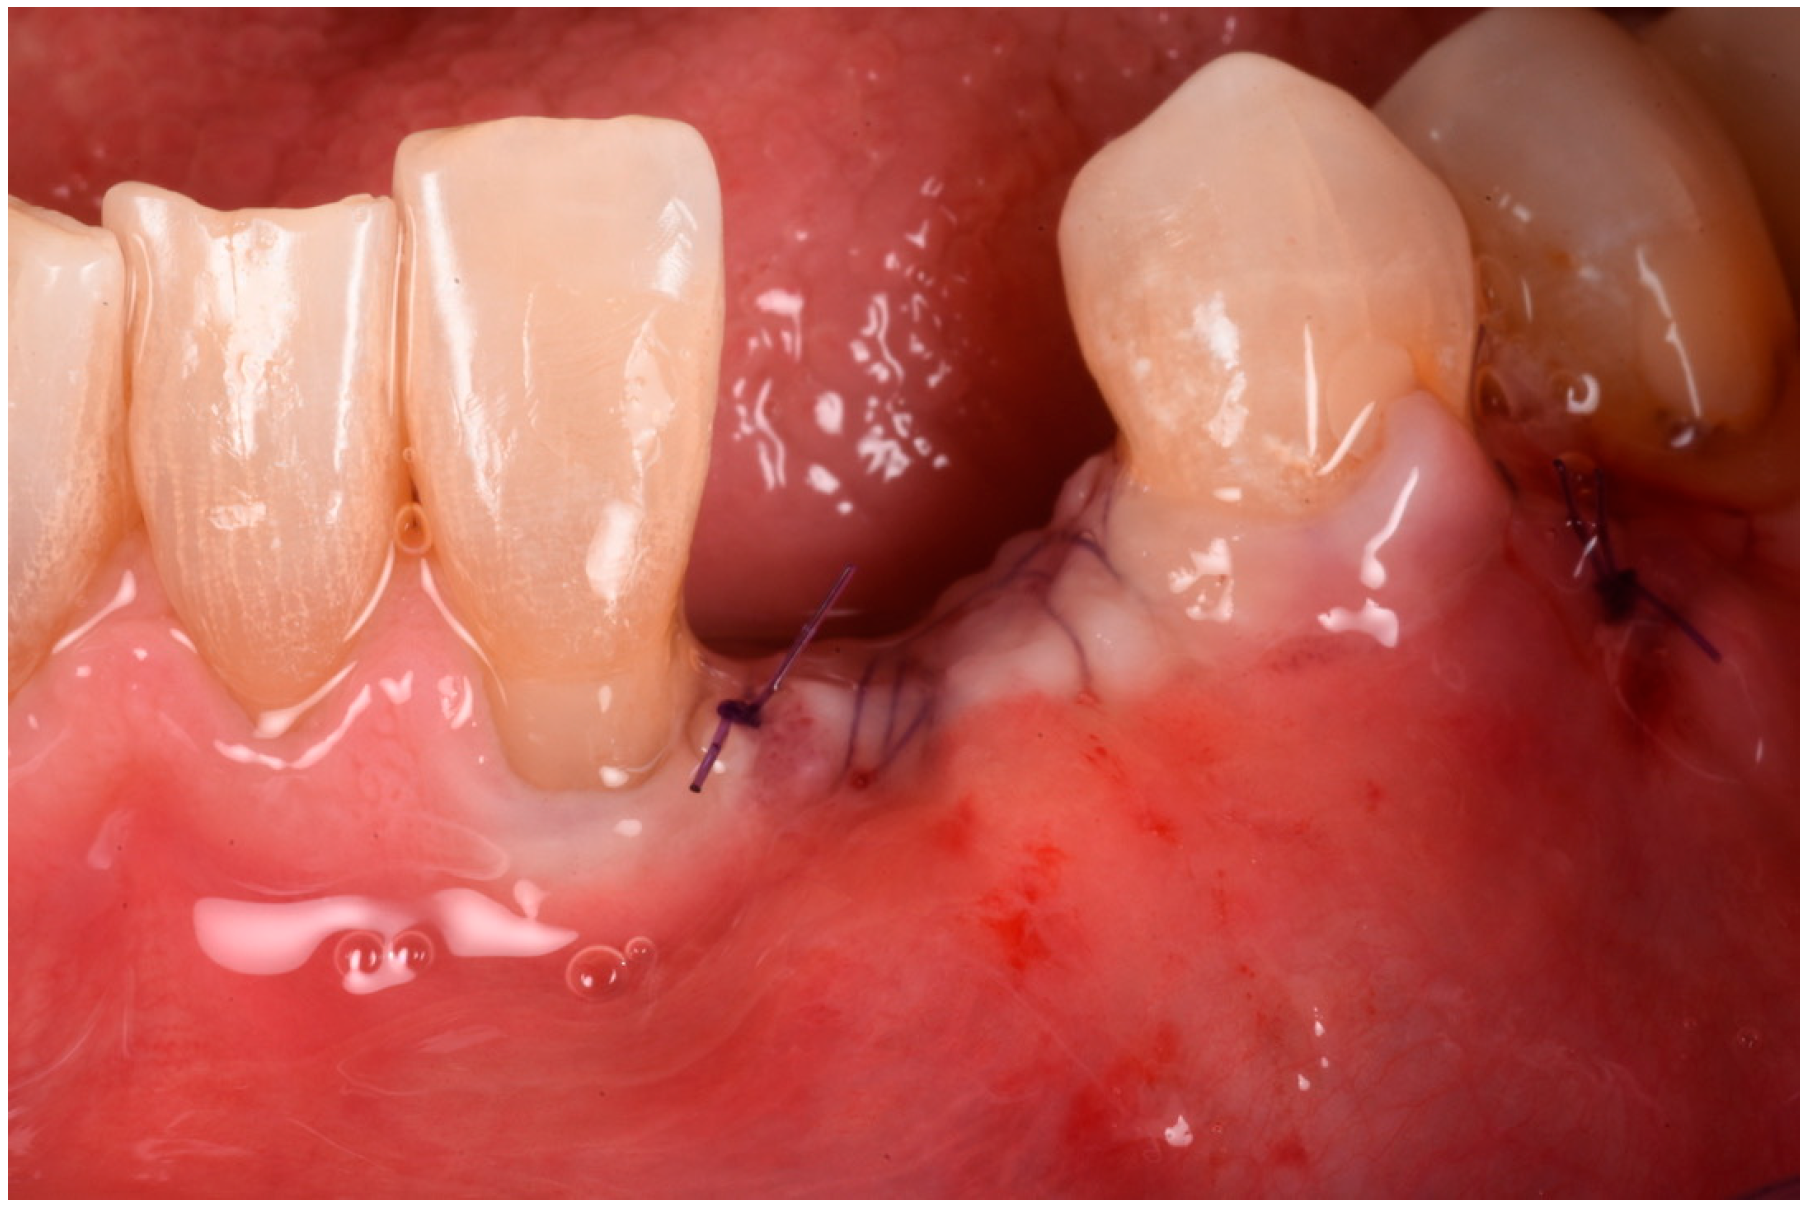

Figure 11. Flaps sutured in place.

Medicina 61 00683 g011

The buccal flap was extended from distal to mesial using a technique known as ‘soft brushing’, performed with dedicated atraumatic instruments. This method allows the flaps to be stretched without sharp incisions, which reduces post-operative edema and results in soft tissues that are well adapted to the new anatomy. To ensure a perfect and tight seal of the flap, 5–0 resorbable sutures (two double-sling sutures at the mesial and distal papilla and a horizontal locking mattress in the middle of the ridge) were used (Flysorb Mono Butterfly, Cavenago di Brianza, MB, Italy), protecting the augmented site (Figure 11). The post-operative protocol included amoxicillin 1 g twice daily for a week, ibuprofen 400 mg as needed for discomfort, and gentle rinsing with 0.2% chlorhexidine spray once a day. Eight months post-surgery, healing was uneventful, with soft tissues appearing at the same level as on the surgical day. Concurrently, a CBCT was performed to assess the degree of healing and integration of the xenografts and to plan the insertion of the implant. The CBCT results indicated a good degree of mineralization, suggesting it was time to position the planned implant (Figure 12).